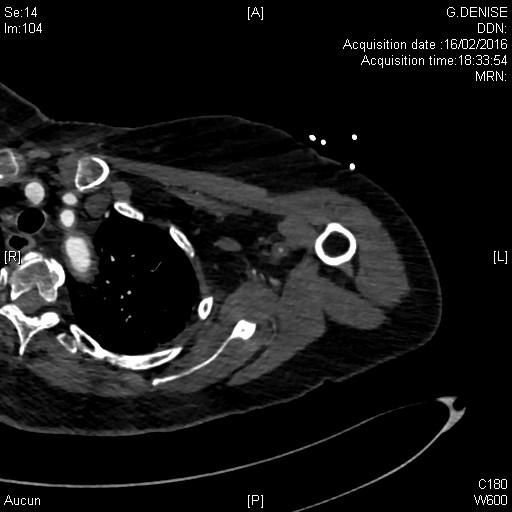

Aortite et sténose de l'artère axilaire gauche dans le cadre d'une artérite à cellules géantes